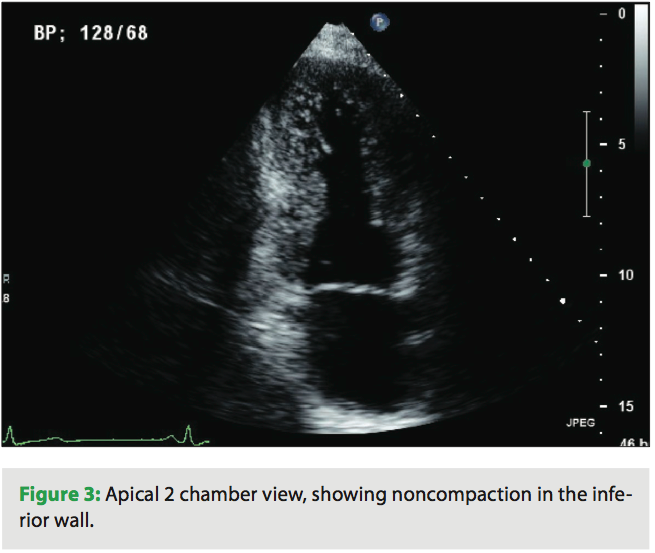

A 39-year-old female presented to the emergency department with chest pain and palpitations. She was hiking with her husband when the palpitations started and she felt her pulse, which seemed to be fast and irregular. Her pain was in the center chest, sharp with no radiation, but she felt fatigued and tired. She reports a history of being short of breath in the past two months during exercise. Her father died suddenly at age 30 years, but never had an autopsy done. She takes no medications and works as a nurse. Her physical examination revealed a heart rate of 160 beats per minute and her blood pressure was 110/65. Her pulse was irregular, and her ECG revealed atrial fibrillation with left ventricular (LV) hypertrophy. Her labs were normal, and her troponin level was 0.29 ng/mL. An echocardiogram was done and revealed increased LV wall thickness, and she was diagnosed with hypertrophic cardiomyopathy. Her ejection fraction was noted to be 40% with wall motion abnormalities. She was transferred to our center, and by the time she arrived, she was in sinus rhythm. She underwent left heart catheterization, which showed normal coronary arteries. When reviewing her echocardiogram, heavy trabeculations were noted in the apex, inferior wall, as well as the lateral wall (Figures 1–3). She was diagnosed with noncompaction of the left ventricle, with a ratio of noncompacted to compacted myocardium of 2.5/1. She had no other congenital heart defects except for patent foramen ovale.

Two-dimensional echocardiography is the modality most commonly used to diagnose ILVNC. Criteria for diagnoses have been proposed by Chin et al, with a ratio of noncompacted to compacted LV myocardium of 2 to 1 considered diagnostic. This is typically measured at end systole in the parasternal short axis view. The noncompacted segments involve usually the apex more than the base, and are seen mostly in the inferior wall and also in the lateral wall. The right ventricle is involved in 40% of the cases. Wall motion abnormalities, impaired diastolic filling as measured from mitral inflow velocities are also seen. Depressed LV ejection fraction is noted in a lot of patients with LV noncompaction. It is important to differentiate ILVNC from hypertrophic cardiomyopathy (especially the apical variant), dilated cardiomyopathy, arrhythmogenic right ventricular dysplasia and endocardial fibroelastosis. Magnetic resonance imaging (MRI) has been also used for diagnosis. Delayed gadolinium enhancement has been seen in both compacted and noncompacted myocardium. In compacted myocardium, delayed enhancement correlated well with fibrosis, while in the noncompacted segments, delayed enhancement correlated with fibrosis as well as mucoid degeneration of the endocardium.9 MRI offers better spatial resolution and can help assess LV and RV functions, wall motion abnormalities, as well as the ratio of compacted and noncompacted segments, which has been shown to be an important predictor of major adverse cardiac events.